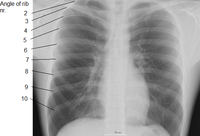

الضلع Rib واحد من العظام الأربعة والعشرين التي تحيط بالصدر في جسم الإنسان. وهناك اثنا عشر ضلعًا في كل جانب من جانبي الجسم، يَتصِل كل واحد منها بالعمود الفقري بوساطة وصلات تسمى الفقرات. وفي مقدمة الجسم، ترتبط الأضلاع السبعة العلوية في كل جانب مباشرة بالعظمة الصدرية بوساطة مادة صلبة مطاطية تسمى الغضاريف، وتُسمى هذه الأضلاع، الأضلاع الحقيقية. أما الأضلاع الخمسة التي تحتها وتُسمى الأضلاع الإضافية، فليست مُتصلة بعظمة الصدر بشكل مباشر، بل إن كل واحد من الأضلاع الثلاثة العلوية الإضافية، مُتصل بالضلع الذي يعلو الغضروف. أما الضلعان اللذان يقعان في الأسفل، فإنهما مُتَصلان بعظمة الظهر. ويُعرفان باسم الضلعين السائبين. وتحتوي الفراغات الموجودة بين الأضلاع، والتي تُسمَّى فراغات بين الأضلاع، على الشرايين والأوردة والعضلات والأعصاب.

تقسيم الاضلاع في الإنسان

- أول سبعة أزواج من الاضلاع تسمى "الأضلاع الحقيقية". وهي متصلة بسشكل مباشر بعظم القص.

- ازواج الاضلاع الثلاثة التالية تسمى بالأضلاع الكاذبة " وهي تتصل بعظم القص بواسطة غضروف.

- اخر زوجين من الاضلاع تسمى " الأضلاع السابحة " وهي متصلة بالعمود الفقري ولا تتصل بعظم القص.